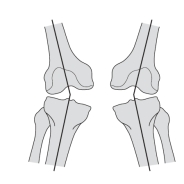

10

-Refer to the figure. The developmental deformity shown here is described as:

A) Bilateral genu varum

B) Bilateral genu valgus

C) Ipsilateral genu valgus

D) Contralateral genu varum